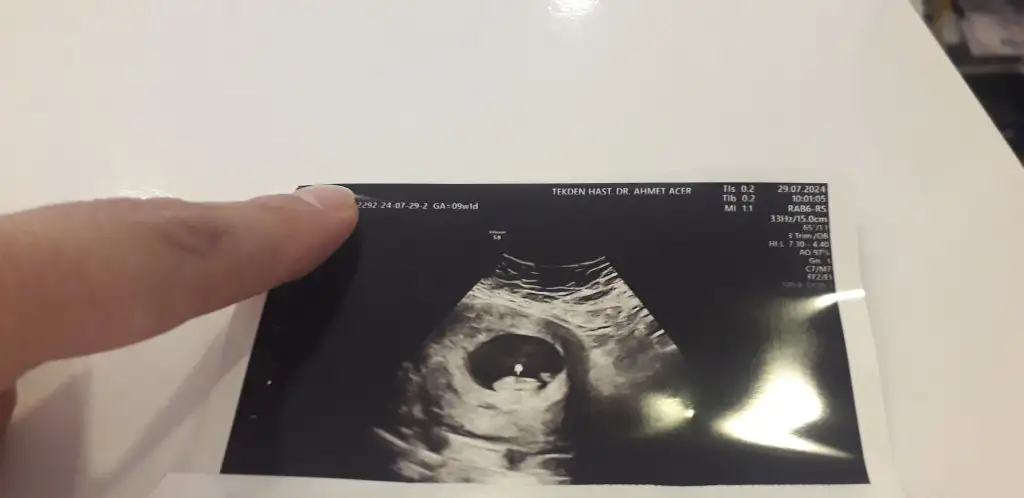

9+1 günlük cinsiyet tahmini yapar mısınız karından bakildi

Eklentiler

• 20240729_124559.webp

20240729_124559.webp

12,5 KB · Görüntüleme: 110